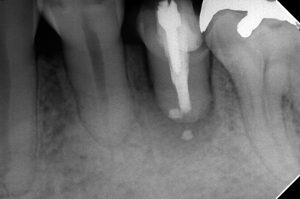

1年半前

右上7番、左上7番、左下5番に病変があります。

主訴は右上7番の痛みです。

これです

頑張って綺麗にし、

MTAを詰めました

MB2もあったようです